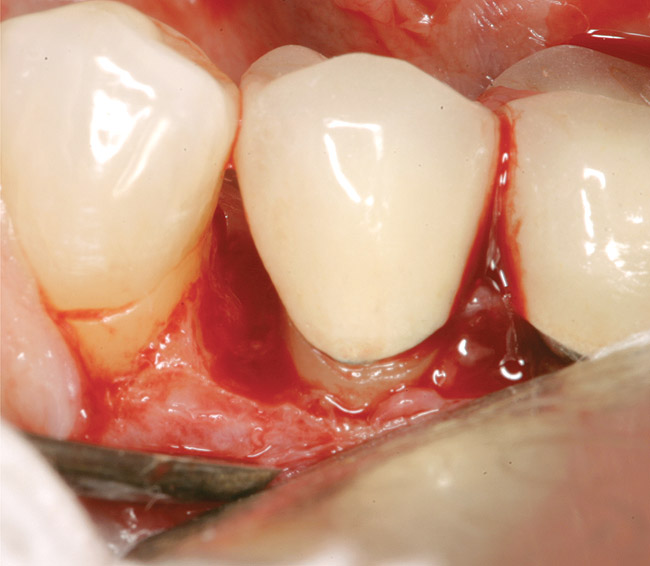

Figure 13  The case seen in Figure 11 on 6-year re-entry showing complete distal bone fill.

Figure 13

Figure 14  Radiographic view of the case seen in Figure 13 showing complete bone fill of the periodontal defect (the bone graft used was mostly radiolucent).

Figure 14

GTR, however, is still a viable option because there is consistency in published data—treating a vertical osseous lesion with this technique results in more clinical attachment gain than just open-flap debridement without performing GTR.46 The success rate in smokers, however, is significantly lower than in nonsmokers.47 Figure 11 and Figure 12] show a case in which tooth No. 22 had a large distal defect. Figure 13 shows the 6-year re-entry photograph, and Figure 14, the 6-year posttreatment radiograph, demonstrating complete clinical fill of the defect. Factors to consider in GTR include defect size (at least 3 mm to 4 mm), number of defect walls (at least two bony walls, but a three-wall defect is the most predictable to treat; Figure 15 shows a one wall defect, which is not graftable), furcation status (furcations are less predictable to obtain increased clinical attachment levels46), and mobility.48 However, patient compliance is critical in regard to both short-term and long-term success rates with GTR.